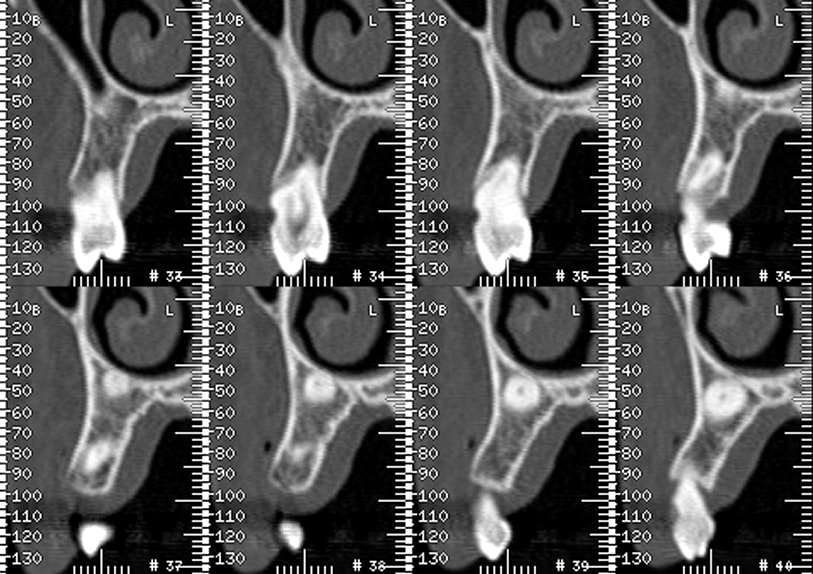

je dois poser un implant en lieu et place de la 13

mais cette 13 est incluse

la patiente a 74 ans

j'ai 6mm